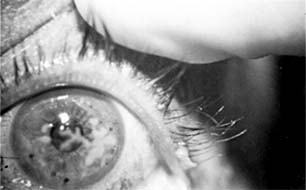

Pneumococcal corneal ulcer usually occurs 24-48 hours after inoculation of an abraded cornea. It typically produces a gray, fairly well circumscribed ulcer that tends to spread erratically from the original site of infection toward the center of the cornea (Figure 6-1). The advancing border shows active ulceration and infiltration as the trailing border begins to heal. (This creeping effect suggested the term "acute serpiginous ulcer.") The superficial corneal layers become involved first and then the deep parenchyma. The cornea surrounding the ulcer is often clear. Hypopyon is common. Scrapings from the leading edge of a pneumococcal corneal ulcer usually contain gram-positive lancet-shaped diplococci. Drugs recommended for use in treatment are listed in Tables 6-2 and 6-3. Concurrent dacryocystitis should also be treated.

Figure 6-1

Figure 6-1: Pneumococcal corneal ulcer with hypopyon.